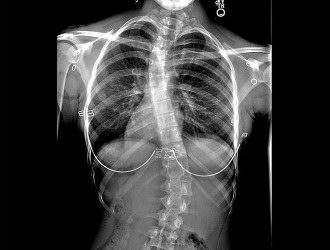

Диагностика заболевания

Существует ряд диагностических мероприятий, позволяющих вовремя определить наличие изменений в позвоночнике:

-

Самое первое и самое главное мероприятие. Единственным минусом является то, что делать рентген чаще одного раза в несколько месяцев нельзя из-за высокого уровня облучения;

Рентгеновский снимок. - Фотографический снимок. Такую фотографию делают на фоне стены в клетку. Врач делает несколько снимков в разных ракурсах: в полный рост спереди, сбоку, в обычном положении туловища;